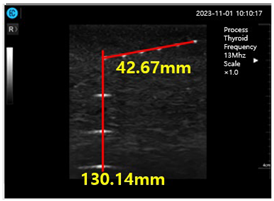

Figure 15a shows ultrasonic gel testing at various time intervals using the ATS-539 phantom. Figure 15b shows the sharpness of the image of the manufactured gelatin soft gel after storing it in alcohol and performing a sharpness test at 1 h intervals for 72 h. The results are presented in Figure 15b. In this paper, the experiment using a soft solid gel did not require IRB agreement. This research on the proposed gelatin soft solid gel showed its functionality to be better than that of ultrasonic gel, including on grayscale, echo, and color. This means that it can overcome the tissue density dead zone to increase high resolution performance. To help imaging accuracy, it is proven that gelatin soft gel, especially the soft solid gel, can replace ultrasonic gel to simplify disinfection and ensure permanent use. Image corrosion testing of gelatin soft solid gel for 30 min is shown in Figure 16a. Ultrasonic gels were tested at different times using an ATS-539 phantom, where the gel was soaked in ethanol for 72 h, as shown in Figure 16b. Afterwards, the gel’s condition was tested again. Finally, Figure 16c measures the imaging resolution of the gelatin soft tissue gel.